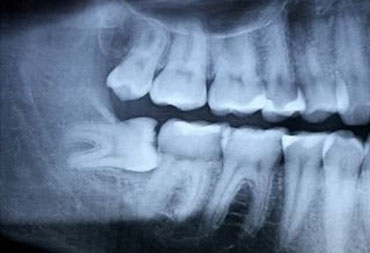

Should you get that retained wisdom tooth out? Scared about costs and procedure?

Dr Andreas Schwander has a special interest in wisdom tooth and other oral surgery. He looks back at over 20 years of experience in this field with even the most difficult retained teeth.